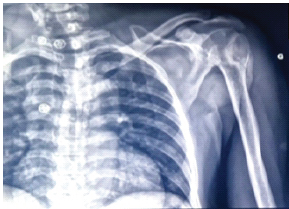

Bilateral Shoulder Dislocation with Fracture of Major Tubercles – A Case Report

Layes Touré , Moussa Sidibé , Térédjou Fatou Sanogo , Aliou Bah , Abdoul Kadri Moussa

………………………………p.217-220